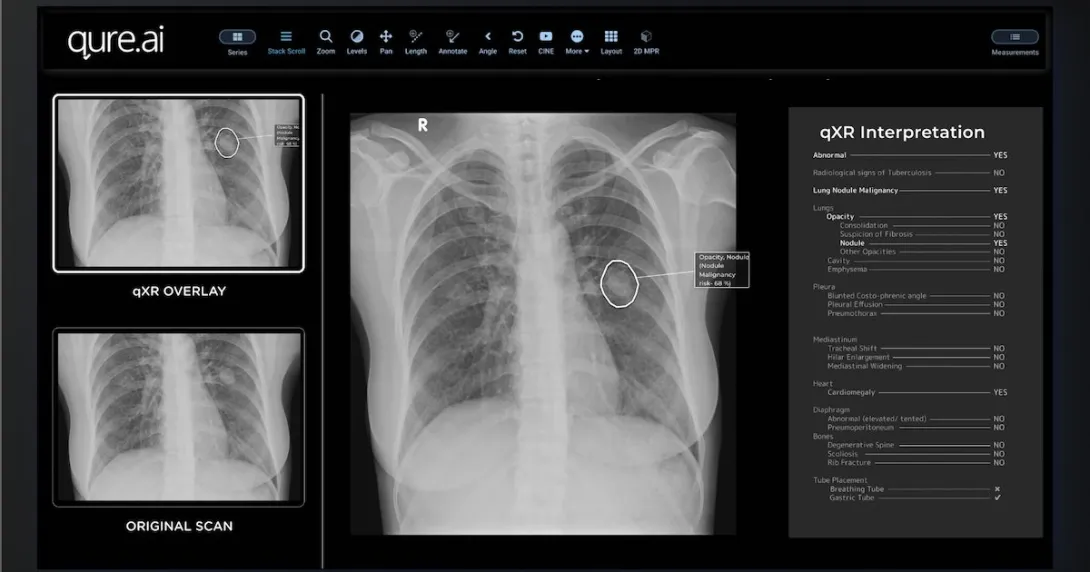

Qure.ai's qXR software will enable Mylab's upcoming x-ray device to quickly detect TB.

Qure.ai's qXR software for the detection of abnormalities in chest x-rays

Photo courtesy of Qure.ai

According to a press statement, MyBeam is a compact, lightweight device equipped with high-frequency technology for detecting TB. It will be powered by Qure.ai's deep-learning software qXR to analyse chest x-ray images and identify TB within a minute.